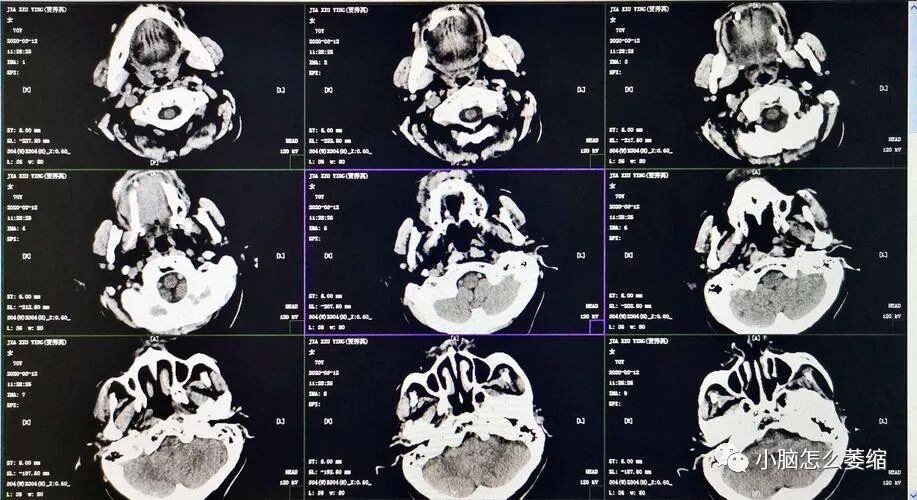

在医学领域,小脑萎缩是一种常见但严重的神经退行性疾病。这种疾病会引起患者的小脑组织逐渐萎缩,导致运动协调能力下降,甚至出现严重的行动和语言障碍。然而,近年来,一位勇敢的患者通过积极治疗和坚持不懈地努力,成功重拾了健康的生活。

患者用药三个疗程后,头晕情况近一月没有出现,眼睛看东西不模糊了,耳鸣减轻了,口干口苦基本没有、流口水基本没有了,四肢无力感减轻了,整体的精气神要比用药前好上许多,患者为巩固病情不让其继续发展,甚至抱有好转的心思,继续服用。六个疗程后,症状基本改善,身体有力气了,自己可以适当性的做一些运动,走路比以前稳多了,现已停药观察。